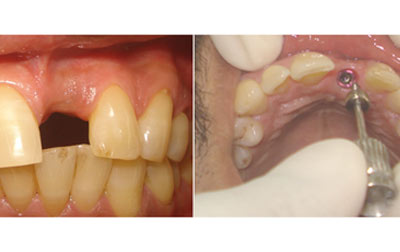

Nobel Implants- Nobel Implant is a breakthrough in dental restoration. Crafted with precision, the Nobel Implant offers a seamless solution for missing teeth, ensuring both functionality and aesthetics. Engineered from biocompatible materials, it seamlessly integrates with your jawbone, providing stability and long-lasting support. Our seasoned specialists meticulously execute the implant procedure, employing state-of-the-art technology for optimal results and minimal discomfort. Experience restored confidence in your smile, improved speech, and enhanced chewing capabilities. Say goodbye to discomfort and slipping dentures. With Nobel Implant, embrace a natural-looking, permanent solution that redefines your dental well-being, one smile at a time.

All-on-four Implants-The All-On-4 dental implant technique revolutionizes tooth replacement by utilizing only four implants to support an entire upper or lower set of teeth. This innovative approach involves strategically angling the posterior implants at a 45° tilt towards the back of the mouth. These implants are then precisely positioned within the front part of the upper jaw (anterior maxilla), a region known for its denser bone structure. What sets the All-On-4 method apart is its ability to provide stable implant support even in cases where bone density might otherwise be insufficient for traditional implant procedures.